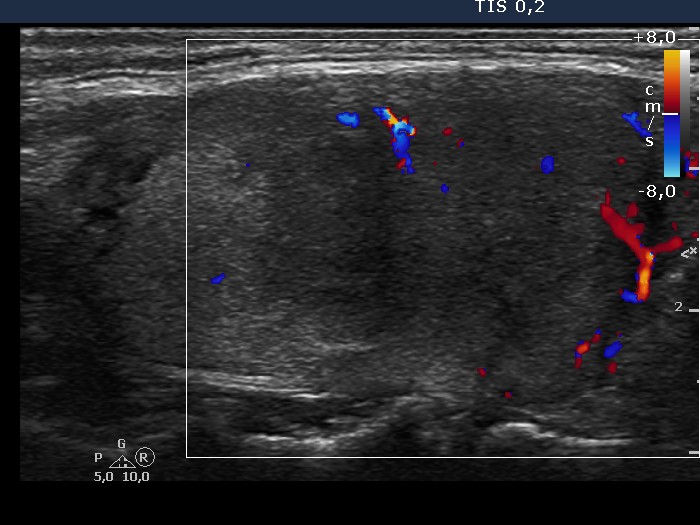

The borders of the nodule - case 1454 (ultrasonographic picture 4)

Right lobe, longitudinal view, color Doppler mode.